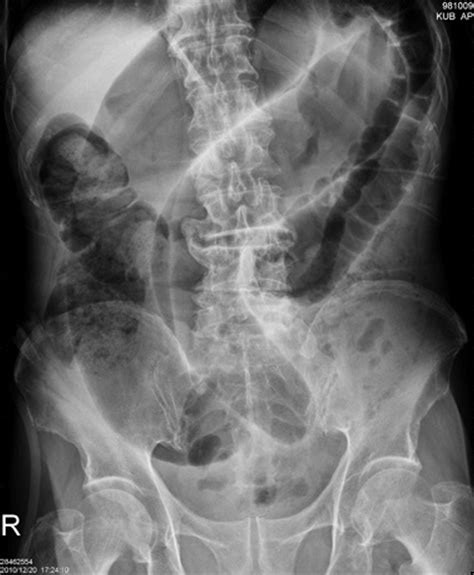

- volvulus coffee bean sign

- coffee bean sign axr

- coffee bean sign meaning

- coffee bean sign radiopaedia